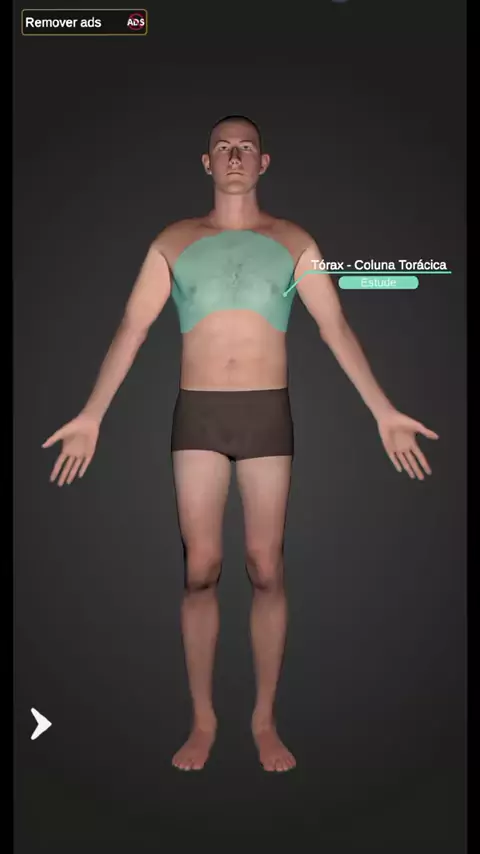

Posicionamento do Tórax rotina em PA + PERFIL ☢️ #técnicoemradiologia #estágio #raiox #tórax #radiologia